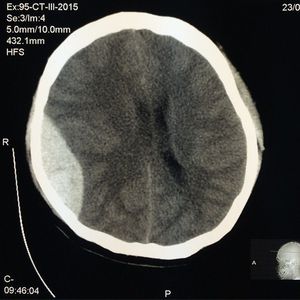

Epidural hematoma